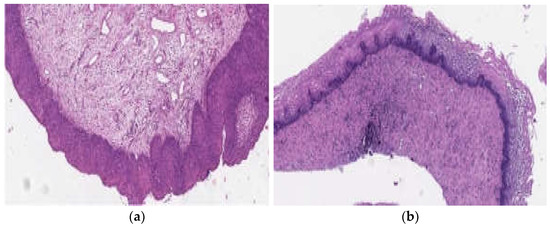

Figure 3 shows histological preparations of a patient with a CIN III/HSIL lesion. As can be seen, 5 weeks after phototheranostics, there are no signs of a cervical intraepithelial squamous lesion.

Figure 3. Histological preparations of a patient with HSIL\CIN III. Hematoxylin–eosin. Boost 90: (a) before phototheranostics and (b) 5 weeks after phototheranostics.